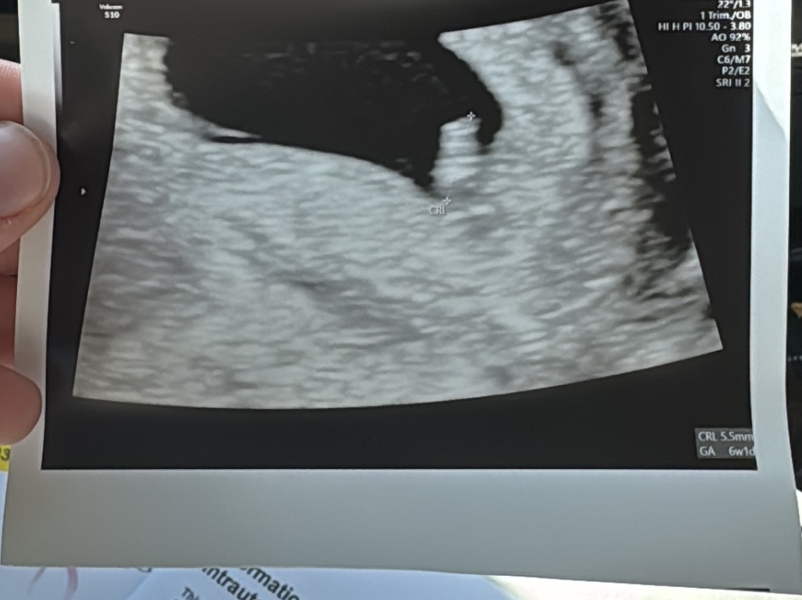

The scan went well and so relieved all looks ok, even saw a little heartbeat on the screen ❤️ attached the pic as sensitive in case anybody doesn’t want to see.

@jennacx ah thats so cool! So so happy for you! :) How many weeks are you? Thinking of booking a scan but worried Im too early at 6+3/

My calculations are 6+5 but they said I’m measuring at 6 weeks exactly. I managed to see a little flicker of a heartbeat so hopefully you would see something too given roughly the same sort of time xx it was a transvaginal scan rather than an ultrasound xx

Hi everyone just a little update. Went to the EPU today and had a scan. Measuring 6+3 when originally I was told I’m 7 weeks. Apparently normal for those with long cycles. Heart was beating away - I’m so excited and a lot less panicked now! AND there was only one in there THANK HEAVENS! Picture attached but marked as Sensative for anyone that doesn’t want to see xxx hope you are all well xxx